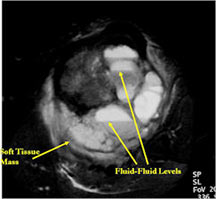

- The cystic spaces filled with hemorrhagic material leads to the presence of fluid-fluid levels on MRIs (so called ABC-like changes or telangiectatic change)

- ABC- like changes can sometimes lead to a misdiagnosis on X-rays and the tumor may be misinterpreted as being a benign ABC.

MRI/CT:

- Fluid-fluid levels secondary to cystic cavities filled with blood products. The sediment from blood products settle to the gravity dependent area of the cavity and the fluid component floats to top thus forming a fluid-fluid level.

- MRI and CT are also useful for demonstrating the local extent of the tumor and any soft tissue mass